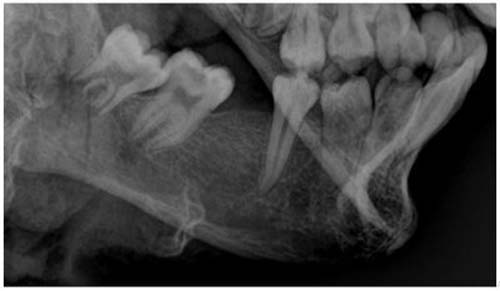

O perito odontolegista João Alfredo Guimarães, responsável pelo exame, explicou que o corpo foi escaneado e as imagens produzidas da arcada dentária foram utilizadas para analisar e comparar com a ficha dentária e as fotos da vítima. Também foi possível fazer a estimativa da idade do corpo, através da cronologia da formação dos dentes, e analisar alguns detalhes da arcada, como a posição dos dentes frontais e a extração de um dente que constava na ficha odontológica.

“Durante o exame odontolegal no corpo do cadáver identificamos várias evidências como idade estimada, ausência dentária e posição dentária compatíveis com aqueles encontrados na certidão de nascimento, documentação odontológica e fotos pertencentes a vítima. Todos esses achados periciais permitiram concluir que se trata da mesma pessoa, ou seja, a vítima realmente era o adolescente Mateus Lima”, afirmou o odontolegista.